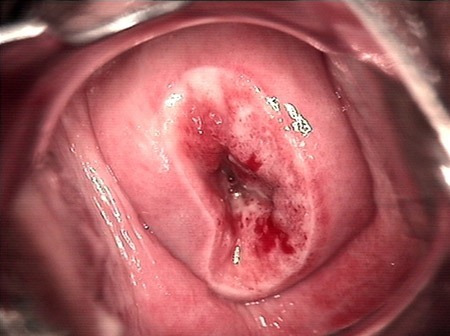

CIN 2-3 leep術(shù)后